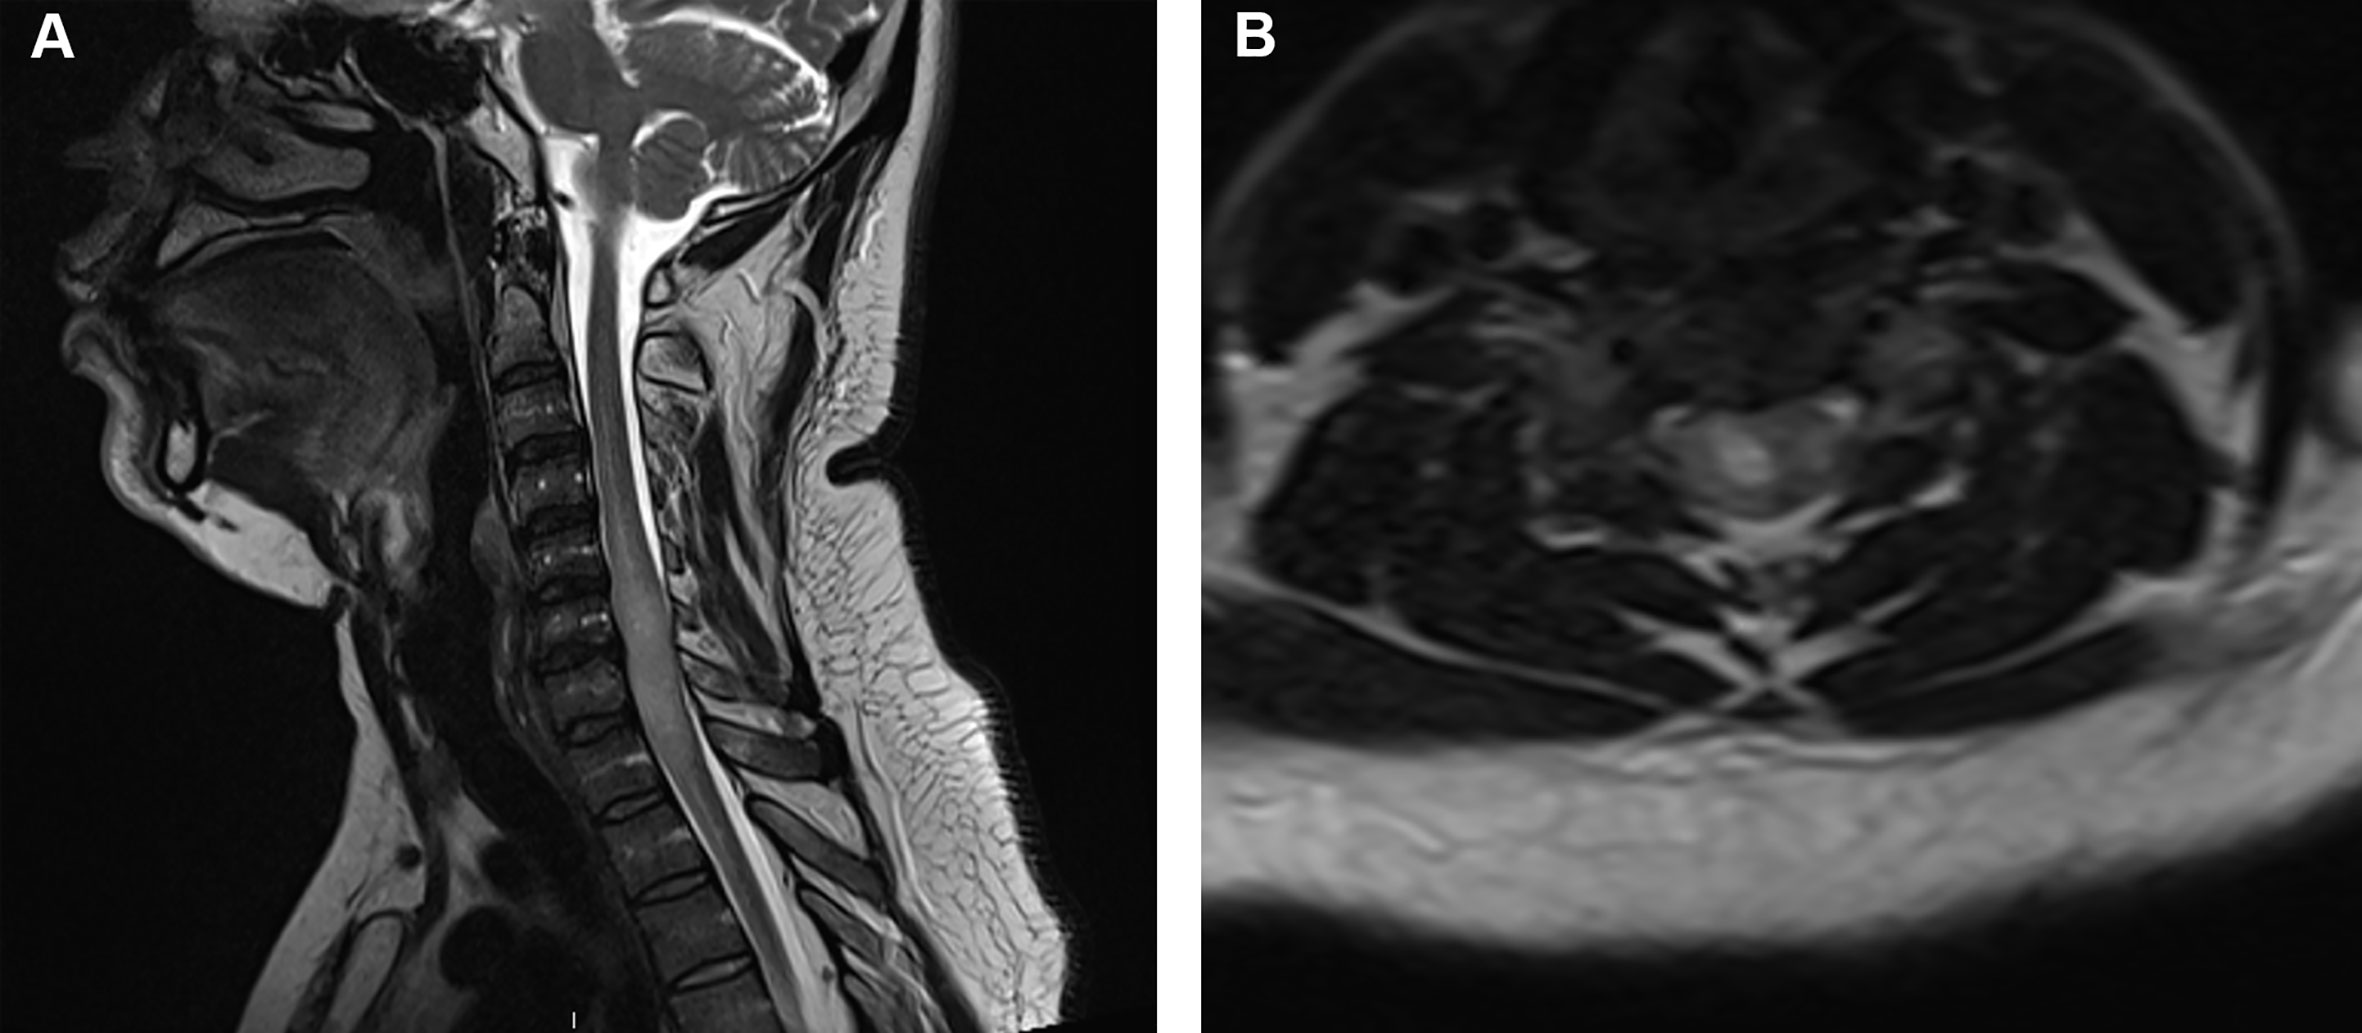

spinal meningioma

well circumscribed

dural attachment (dural tail sign)

homogeneous enhancement

spinal schwannoma

arise from spinal nerve roots

differentiated from spinal meningioma by lack of dural tail